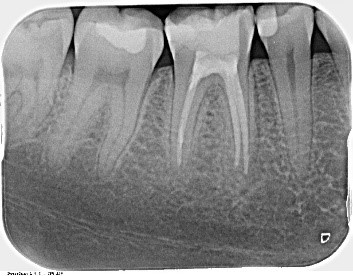

Eine Wurzelbehandlung ist immer dann notwendig, wenn sich der Nerv entzündet hat und diese Entzündung den Nerv unwiderruflich geschädigt hat. Früher war das ein Extraktionskriterium und der Zahn musste oftmals der Zange weichen. Heute ist man bemüht durch modernste diagnostische Methoden und neue Aufbereitungstechniken den Zahn so lange wie möglich zu erhalten und im besten Fall die Entzündung vollständig zu besiegen. Da der Wurzelkanal ein kompliziertes und sehr individuell angelegtes anatomisches Gebilde auf kleinstem Raum darstellt, fordert die Behandlung des Kanalsystems nicht nur ein adäquates Equipment wie elektronische Messverfahren, Vergrößerungsoptiken, Röntgendiagnostik, sondern auch verschiedene Möglichkeiten der Fülltechnik, eben abgestimmt auf die jeweilige Krümmung der Wurzel.